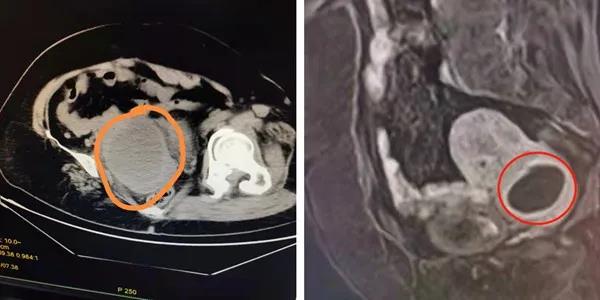

入院后,为进一步确认张阿姨的情况,行盆腔增强磁共振,提示:子宫下段宫颈前壁肌层内病灶,约4公分,不排除脓肿。完善各项术前检查,顾爱玲主任诊查病人后分析:患者发病已有一月,起病有发热、外院抗感染治疗有效,考虑盆腔感染明确。但几次检查结果均不一致,这移动的、会跑的盆腔包块,究竟是什么?实属罕见!

△图左:查急诊CT提示宫腔内病灶

△图右:增强磁共振MRI提示宫颈肌层内病灶